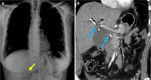

Endoscopic retrograde cholangiopancreatography (ERCP) is a cornerstone procedure for the diagnosis and management of pancreatic and hepatobiliary diseases. Although its diagnostic role has been increasingly supplanted by noninvasive imaging modalities such as magnetic resonance imaging (MRI) and magnetic resonance cholangiopancreatography, the therapeutic applications of ERCP have continued to expand. ERCP is widely used and has a generally favorable safety profile. However, it is important to recognize expected post-procedural imaging findings and serious complications that can arise. The increasing complexity of therapeutic interventions and the growing volume of procedures have led to a higher incidence of complications that often present with overlapping clinical and laboratory features, underscoring the critical role of imaging in differential diagnosis. This review focused on the typical normal ERCP findings and the imaging characteristics of common complications, including pancreatitis, bleeding, ERCP-related infections, perforations, and stent-related complications. Computed tomography (CT) is particularly valuable in timely recognition, management, and surgical decision-making for these complications. Furthermore, MRI offers a radiation-free alternative for managing complications in selected patients. Therefore, radiological modalities, particularly CT and MRI, are critical tools for the rapid diagnosis, management, and surgical decision-making processes for post-ERCP complications.